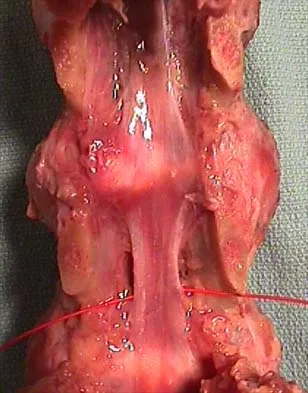

Optimal management of the injury shown in Figure 31 should include which of the following?

Explanation